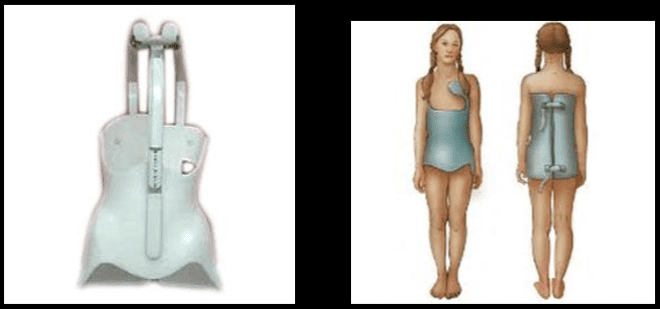

Jappoġġja l-Ġenb

Pazjenti li jbatu minn uġigħ fid-dahar kroniku baxx minħabba proċessi deġenerattivi fuq livelli multipli b'diversi kawżi jistgħu jibbenefikaw minn appoġġ lumbari. Hemm evidenza konfliġġenti rigward l-effettività tagħha b'xi studji li jitolbu titjib moderat fl-eżenzjoni immedjata u fit-tul filwaqt li oħrajn ma jissuġġerixxu l-ebda titjib bħal dawn meta mqabbla ma 'metodi oħra ta' trattament. L-irfid tal-ġenbejn jista 'jistabbilizza, jikkoreġi d-deformità, inaqqas il-forzi mekkaniċi, u jillimita l-movimenti ta' l-ispina. Jista 'jaġixxi wkoll bħala plaċebo u jnaqqas l-uġigħ billi timmassaġġja ż-żoni milquta u tapplika s-sħana.